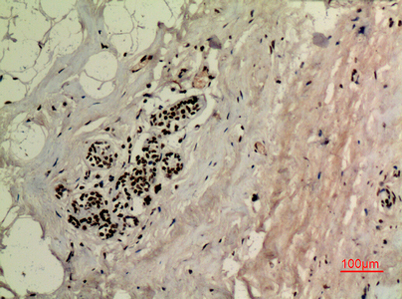

p53 (Acetyl Lys370) rabbit pAb

Product name: p53 (Acetyl Lys370) rabbit pAb

Dilutions: Western Blot: 1/500 - 1/2000. IHC-p: 1:100-300 ELISA: 1/20000. Not yet tested in other applications.

Immunogen: The antiserum was produced against synthesized Acetyl-peptide derived from human p53 around the Acetylation site of Lys370. AA range:331-380